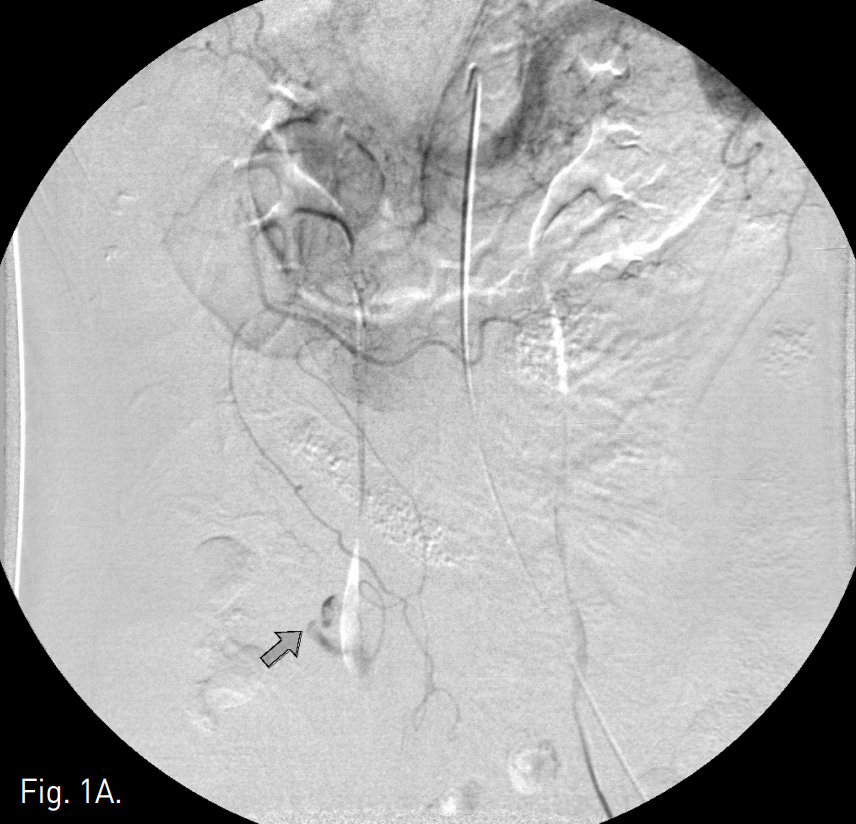

Fig. 2

B. After successful embolization with a 3-mm microcoil, extravasation of contrast media disappeared on the post-embolization angiogram (arrow).